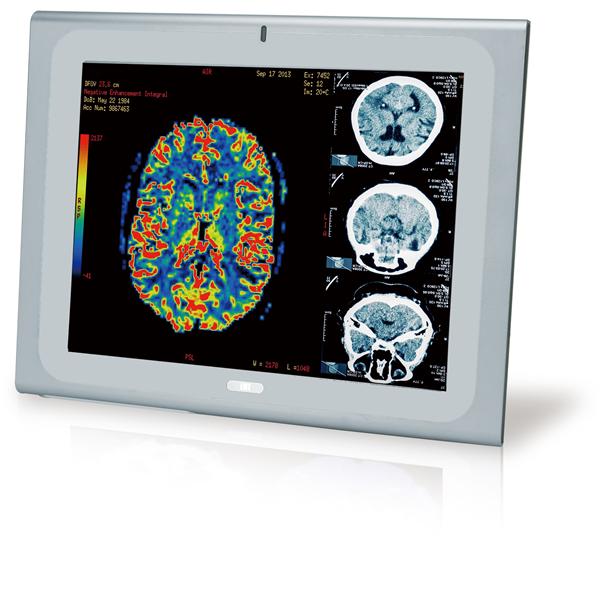

IEI Technology | Panel PCs 21.5" 250cd/m FH... |

IEI Technology | Panel PCs 17" Medical Pan... |

IEI Technology | Panel PCs 19" Medical Pan... |

IEI Technology | Panel PCs 17" Medical Pan... |

IEI Technology | Panel PCs 19" Medical Pan... |

IEI Technology | Panel PCs 17" Medical Pan... |

IEI Technology | Panel PCs 19" Medical Pan... |